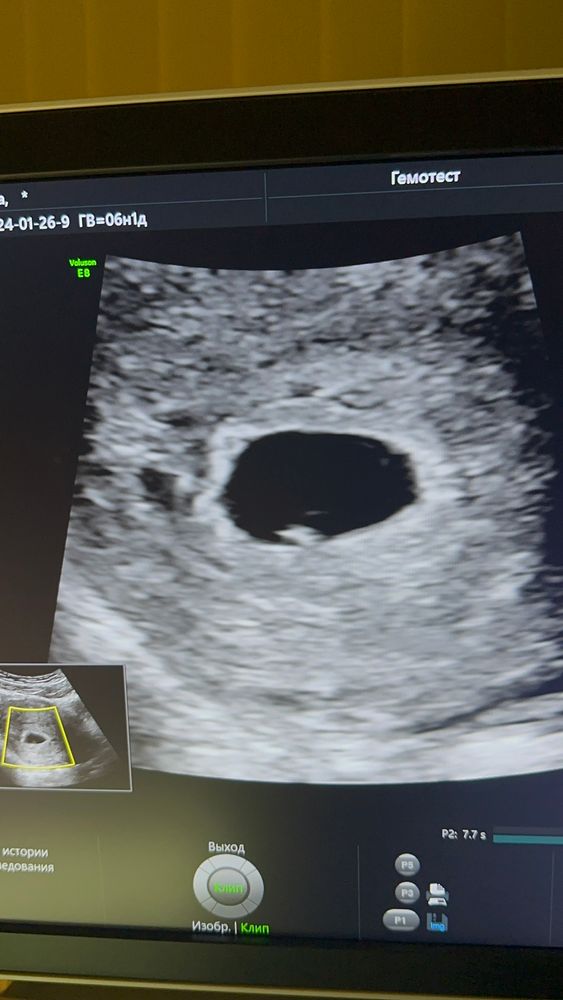

6 недель, полет нормальный

26.01.2024